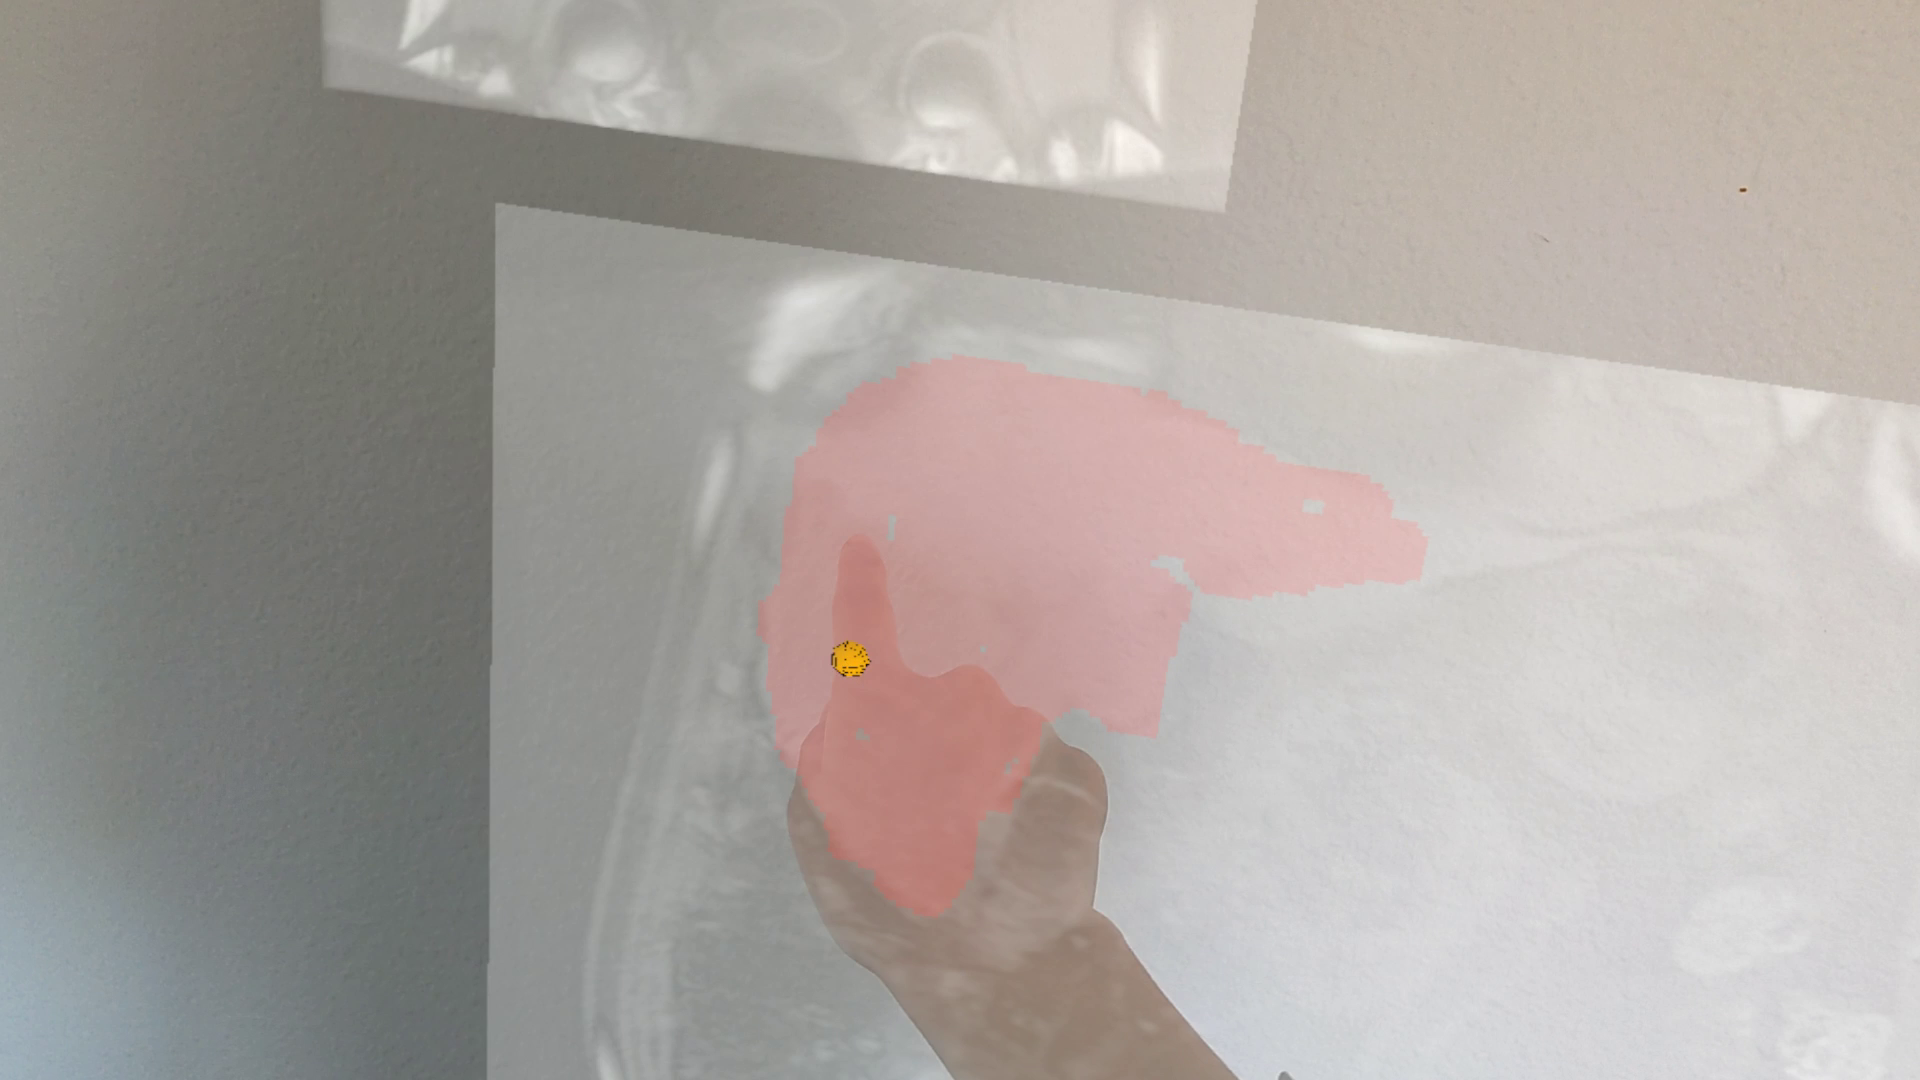

We transformed this concept into AR. As the index finger plunges into the virtual canvas, the hand-unaligned distance (d𝑑d) determines the pen pressure on the canvas. The deeper the finger goes, the more pressure will be on the canvas (Equ.1). Then with a linear pressure sensitivity function, we map the virtual pressure to the sketch stroke size for planar data annotation (Fig. 8).

Refer to caption

(a)

(b)

Figure 8: Virtual-force sketch for 2D data annotation: (a) screenshot of 2D sketching; (b) side-by-side illustration of the volume and annotation data.